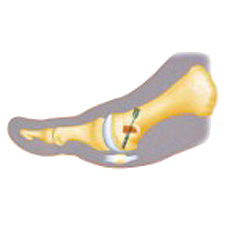

L'hallux valgus est une déviation du gros orteil, aussi appelé "oignon" entrainant une déformation de l'avant du pied. Ce défaut provoque généralement douleur et difficulté à la marche et touche plutôt les femmes. Il devient difficile de se chausser surtout lorsque la déformation devient importante.

C'est une déviation importante du gros orteil vers le deuxième orteil qui correspond à une déformation au niveau du premier métatarsien et biensûr entraine dans la plupart des cas des douleurs de chaussage.

La sévérité de l'hallux valgus dépend de l'angle de déviation et des déformations que cela entraine sur le reste du pied.